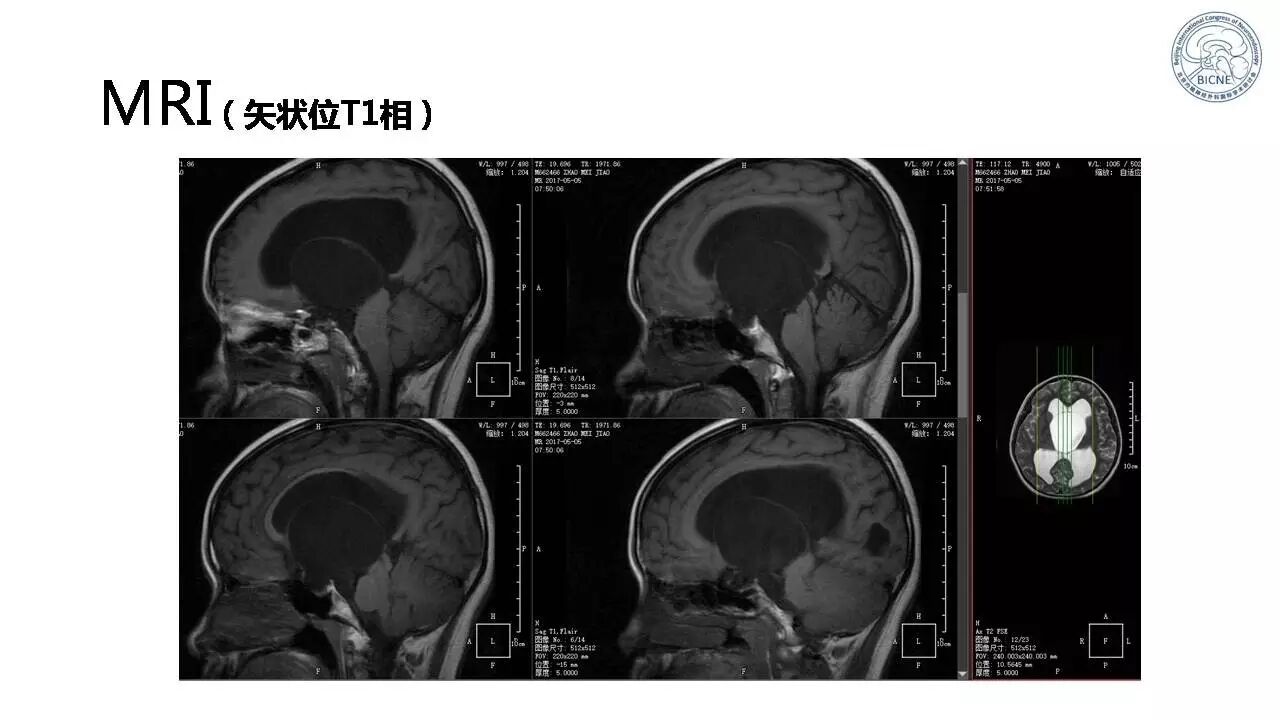

(一)张亚卓教授:脊索瘤经鼻内镜下治疗